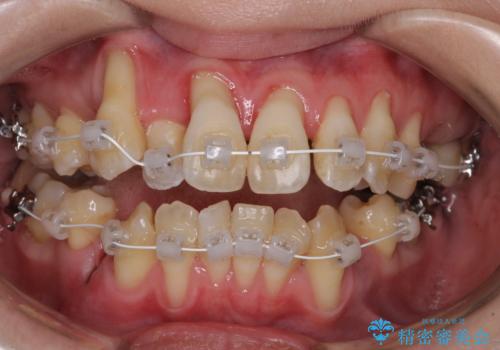

急速拡大装置 狭い骨幅を拡大した上で、顕著なデコボコを改善する抜歯矯正治療

- 前歯のデコボコと唇の閉じにくさを気にして来院された患者様です。

上顎骨よりも下顎骨の幅が広く、更には下顎骨が左側に変位していたため、より良い咬み合わせを達成することを目的として、急速拡大装置を用いて上顎骨を拡大することとしました。

デコボコが強い上に、口元の突出感も気にしていたため、上下左右の小臼歯4本を抜歯して、ワイヤー装置にて矯正治療を行うこととしました。

歯根露出が顕著であったため、歯の移動は早く、スムーズに治療を終えられるかと思いましたが、歯槽骨が硬く、治療は長期間に及びました。

過剰に力をかけ続ける事態となり、一部の歯では変色したり、神経が失活したりとトラブルが続きました。

それでも当初とは比べものにならないほど、綺麗な歯列に仕上げることができました。